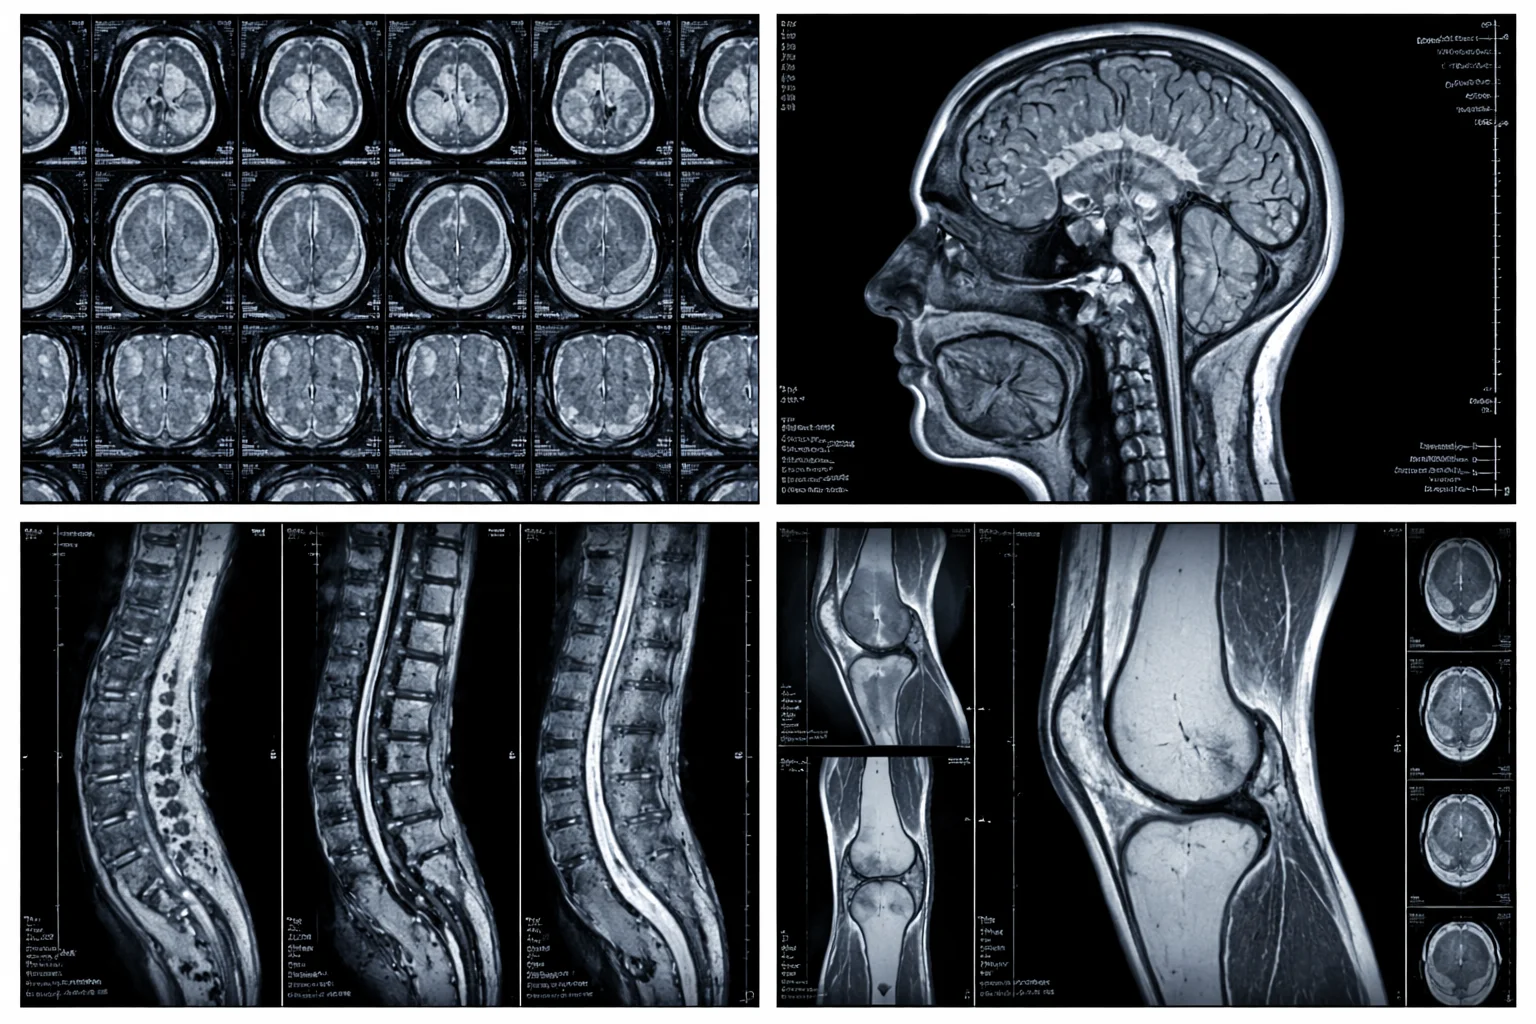

MRI scan results showing cross-sectional images of the brain, spine, and knee

MRI scans can capture images of structures that other imaging methods may not show as clearly, including the brain, spinal cord, muscles, ligaments, and internal organs. They are widely used to investigate a range of conditions, from joint injuries and back pain to neurological concerns and abdominal abnormalities.

MRI scans can cover virtually any part of the body, from the brain to the knees, with the type of scan depending on the condition being investigated.